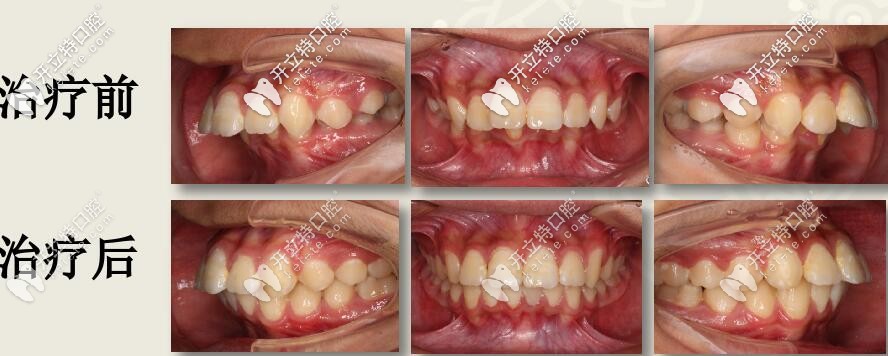

深復(fù)蓋凸嘴伴下巴后縮,直絲弓聯(lián)合擴(kuò)弓,斜導(dǎo)矯正27個(gè)月對(duì)比

12歲兒童齙牙,下巴后縮,牙列擁擠,全口直絲弓配合斜導(dǎo)、擴(kuò)弓器以及激動(dòng)器矯治,27個(gè)月后效果驚人。

今天西安圣貝牙科分享一例12歲兒童齙牙矯正案例,深覆蓋伴隨深覆合,采用雙期聯(lián)合配合肌激動(dòng)器矯治,矯治醫(yī)生是圣貝口腔何曉天醫(yī)生。

肉眼可見上前牙唇傾,輕度擁擠 下頜牙弓寬度窄,前牙區(qū)擁擠,后牙去舌傾明顯,前牙深覆蓋,深覆合

1、安氏Ⅱ類錯(cuò)合

2、骨性二類錯(cuò)合

3、前牙區(qū)深覆蓋、深復(fù)合

4、跨牙合

5、牙列擁擠不齊

結(jié)束后,牙列整齊,深復(fù)蓋明顯改善。